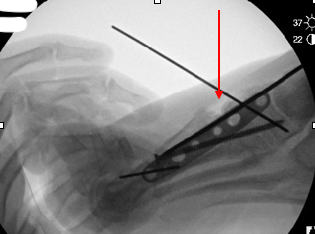

When it comes to harvest of autogenous bone from the posterior tuberosity of the calcaneus, surgeons most commonly utilize this harvest location for procedures in the midfoot and the forefoot.5 The calcaneus is a superior source of bone graft in terms of minimizing surgical time due to its close proximity to the primary surgical site. Calcaneal bone graft is a particularly useful compliment to arthrodesis procedures and fracture repair within the forefoot and the midfoot.

Biddinger and colleagues report that one can harvest up to three, eight mm trephine cores with minimal complication risk.16 DiDomenico and coworkers reported harvest of three to five cm3 of bone from the calcaneus using corticotomy and curettage while adding only two to three minutes of surgical time.17 The risk of sural nerve damage is low with the experienced surgeon but one should take care to avoid irritation in this area.15 Disadvantages of calcaneal bone graft include fracture risk, insufficient quality of bone and postoperative incisional irritation from footwear.18 If the calcaneus is unable to provide a sufficient volume of bone graft, a more proximal site of harvest may be necessary.5 Cross and DiDomenico characterize the calcaneus as a safe harvest site.19

We often utilize autogenous grafting for “positional arthrodesis” procedures. A positional arthrodesis allows for optimal positioning and fixation while often leaving a gap or defect due to translating an abnormal or malaligned position to a more anatomic or aligned position. Often the optimal position does not allow for 100 percent bony contact without the risk of shortening or malposition, thus leaving the surgeon with a bony deficit. One may backfill these defects with autogenous bone graft and maintain adequate positioning. However, we recommend as much bony contact as possible while also obtaining optimal position and maximal stability.

Backfilling a fusion or fracture site allows one to limit the amount of shear-strain across the arthrodesis/fracture site. One can define shear-strain as the angular changes between two line segments. Too much shear or strain across a fusion site will result in failure of the fusion, but a construct that is too stiff can lead to failure as it may not allow enough micromotion to stimulate bony healing.23

For those who prefer maximal primary bony contact during fusion, it remains unclear if there are gaps between bony contact on a microscopic level. Backfilling with autogenous graft during positional arthrodesis facilitates bony spot welding across the fusion site. It allows for deformity correction with some bony contact between the fusion/fracture site while providing structural fixation across the fusion site with a biologically friendly environment. Shear-strain bone grafting allows micromotion to occur in a controlled fashion, thus maintaining position but allowing for increased vascularity and bony healing.24 Perren and colleagues found that primary and secondary bone healing occur at the same rate.24 This concept allows utilization of autogenous grafting not only for reconstructive procedures but also in the setting of trauma.